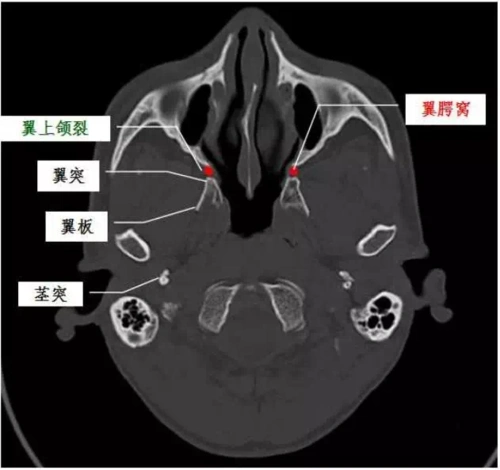

一文搞懂复杂解剖:翼腭窝(必点收藏)